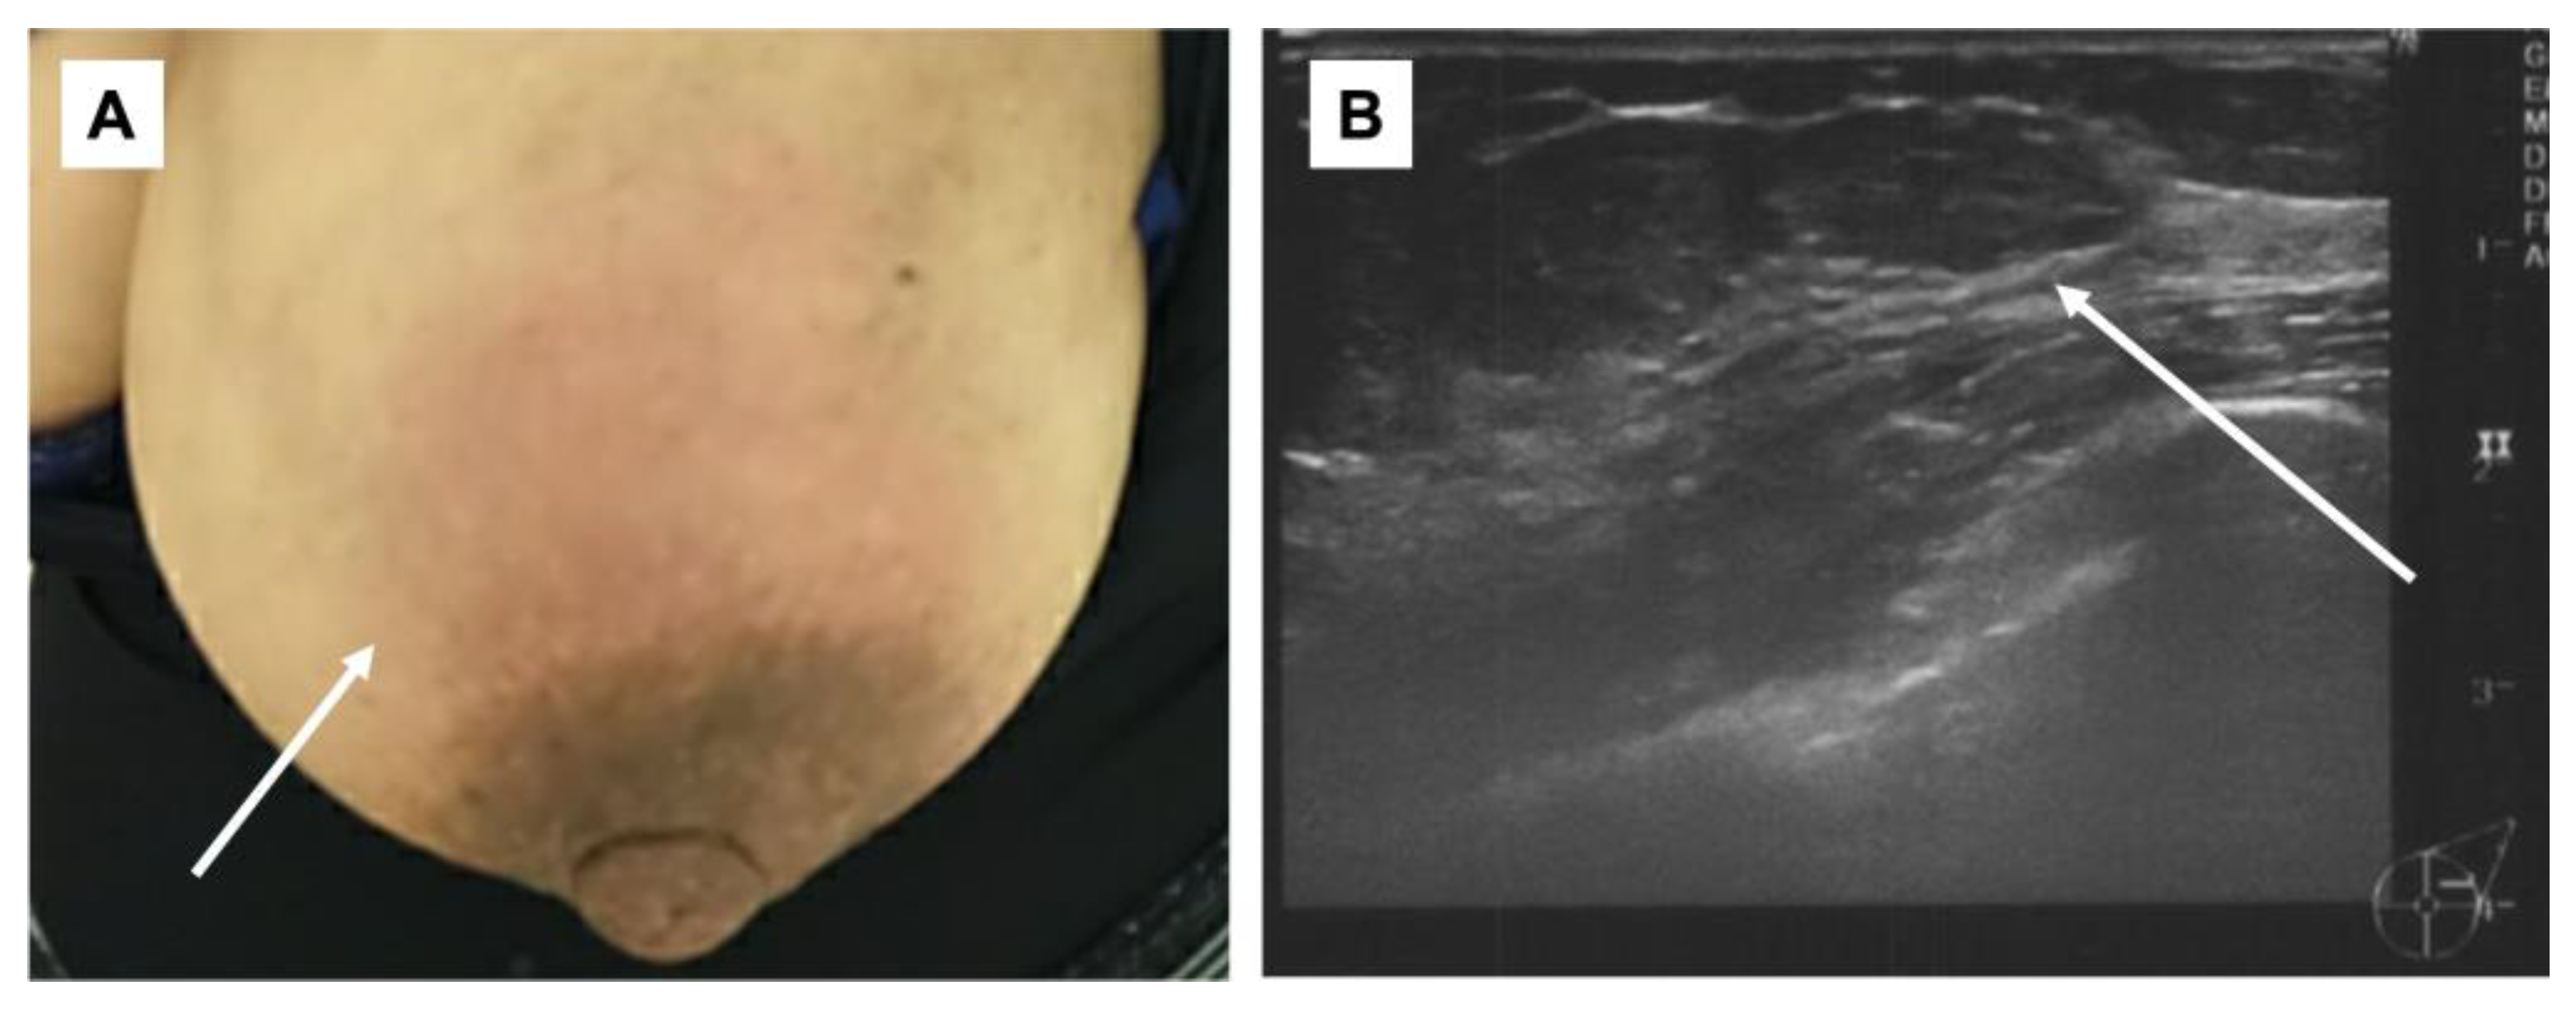

Figure 2.

Physical examination/mammary echography. (A): Redness was observed in the left breast (arrow); (B): internal hypo-absorption area with some dots of hyper-absorption area was observed. The border was clear, and inflammatory disease including abscess was suspected (arrow).

On the second day of the 25th week of pregnancy, the patient developed a tenderness accompanied by erythema on both soles of her feet. Seeking further assistance, she consulted a dermatologist (Figure 1). Initially, the dermatologist diagnosed her with, and treated her for, plantar fasciitis and further prescribed an ointment for treatment. On the same day, the patient was referred to our department for investigation regarding the possible presence of breast cancer owing to a lack of improvement in her symptoms of mastitis. Her height was 155.0 cm and she weighed 59.8 kg. During the physical examination, erythema, pain, and induration were observed in the left breast. Echographic findings suggested pyogenic mastitis (Figure 2A,B). An incision was made to drain the lesion, and a Penrose drain was inserted during the follow-up observation. Cephem antibiotics and anti-inflammatory analgesics were then administered.